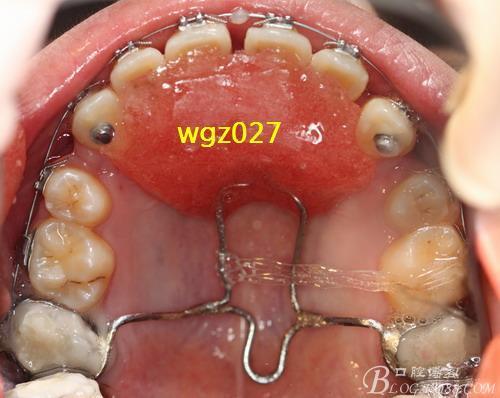

- 上颌牙弓观: 从上方向下看上牙列,观察牙齿拥挤、扭转、弓形等。

- 关键点: 所有照片都必须在相同的角度、光线、头部位置下拍摄,确保与治疗后照片可比。深覆合是拍摄重点,需要清晰展示上颌前牙覆盖下颌前牙的程度(垂直向)。